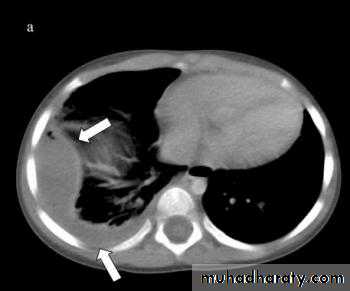

• 6-CT scan

Acute or Exudative phase: Thin pus,Mobile lung(expandable),Thin pleura

Trasitional or Fibrinopurulent phase: Turbid fluid

viscus,thick pleura, Less expandable lungChronic or Organization phase: fluid is viscus,thick pleura,restricted lung

Infection of the pleural space → inflammatory changes → serous exudation → fibrin deposition on the pleural surfaces → invasion by blood vessels from adjacent lung and chest wall → granulation tissue → fibrous tissue → progressive thickening of the wall of the empyema